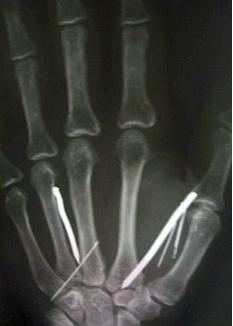

Η 49χρονη Λ.Τ. Αριγιαουάθι επέστρεψε στην πατρίδα της, τη Σρι Λάνκα, και κατήγγειλε τα όσα έζησε στις αρμόδιες Αρχές. Μάλιστα, στο νοσοκομείο όπου νοσηλεύεται, διαπιστώθηκε πως είχε 24 καρφιά στο κορμί της! Τα περισσότερα καρφιά εντοπίστηκαν στα χέρια και τα πόδια της γυναίκας.